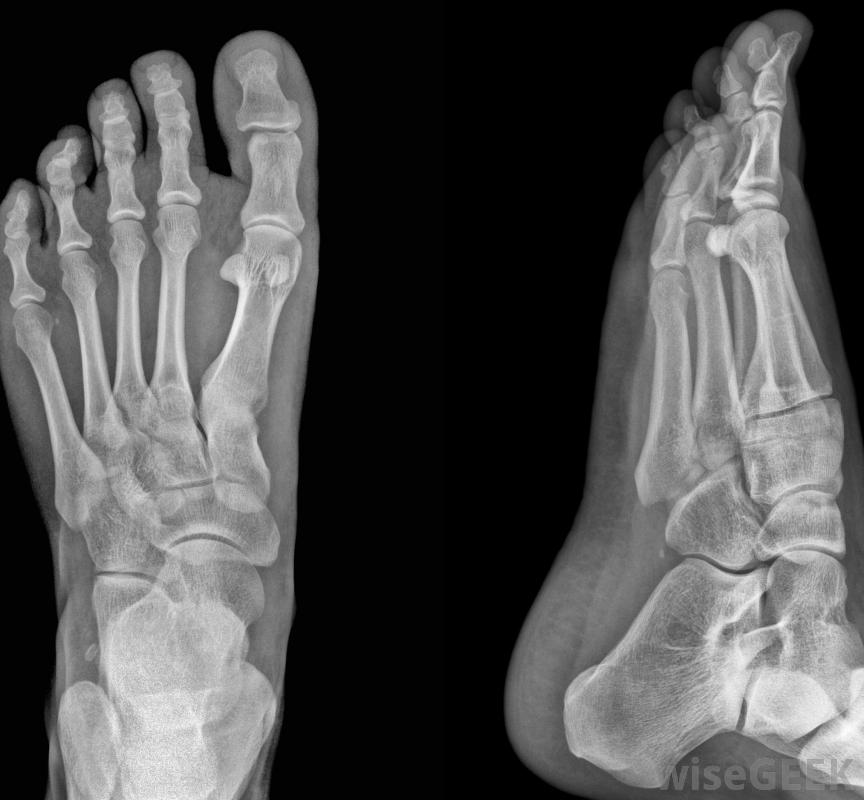

脚趾肿胀限制了行动能力,可能需要去看足病医生当重物落在脚趾上,或在体育活动中脚与物体相撞时,通常会发生脚趾外伤。骨折和瘀伤会导致脚趾肿胀,x光片通常用于确定损伤的严重程度。当创伤导致脚趾弯曲或伸展时,韧带拉伤也可能导致肿胀src="/img/0726/x-ray-of-feet.jpg"/>脚趾骨折会导致脚趾肿胀。那些体力活动的人可能会逐渐拉紧脚趾,尤其是当他们在运动前没有适当伸展,或者运动过度时逐渐紧张引起的脚趾肿胀可能不会立即明显,而且在肿胀出现之前,损伤可能会很严重和疼痛,可能导致视觉浮肿和疼痛,也可能对位于组织和骨骼之间的液体袋造成创伤。脚趾关节也可能肿胀并变得触痛。

可以使用x光检查脚趾头肿胀。脚趾头肿胀不能归因于身体损伤或劳损,这可能是一种疾病的结果。肿胀的脚趾通常与痛风有关,尿酸过多在关节和肌腱中结晶,导致脚趾肿胀、发红、摸起来很烫的情况。其他医学原因包括关节炎、感染和血凝块。医生可以从受影响的关节提取液体来确定病因,这种情况下的肿胀通常可以通过药物或手术治愈或控制。